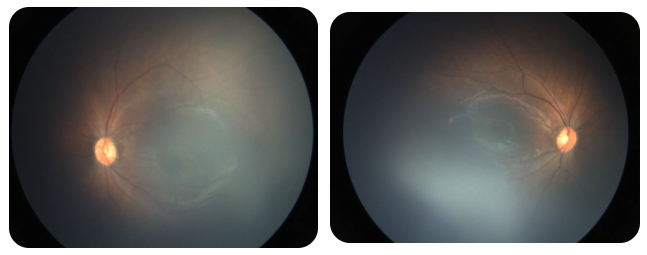

近期術(shù)前檢查:

早產(chǎn)兒視網(wǎng)膜病變

術(shù)后復(fù)查: